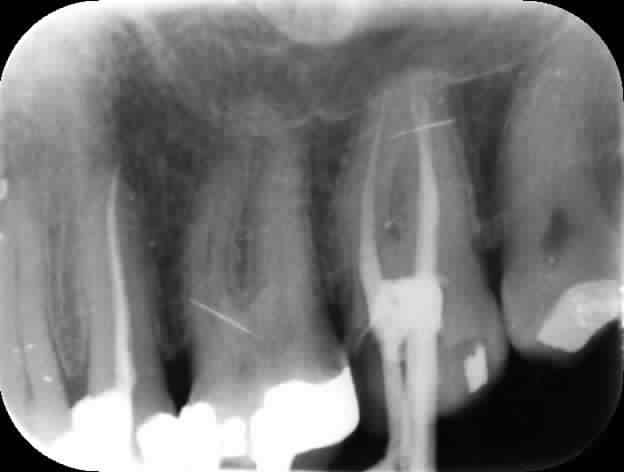

20/12/2014 à 13h11

in vivo 3 ans à l'air libre, monocone scellé, pas de digue : il y a une pèche à l'apex ? non.

6 pvl628 - Eugenol

8 h9nynj - Eugenol